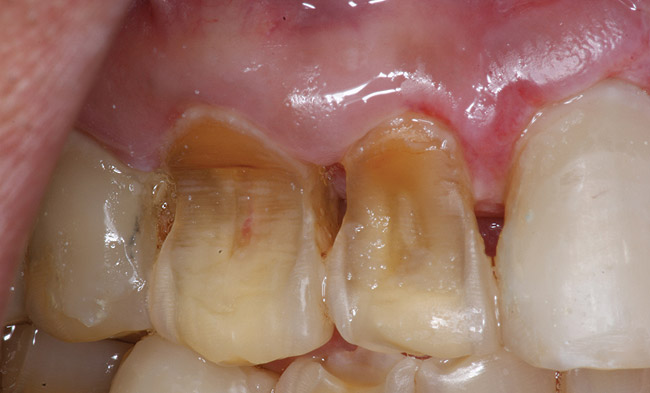

If a patient has risk factors that can contribute to dental erosion, an examination will reveal clinical signs and symptoms of dental erosion. It is unlikely that dental erosion will be seen without other contributing factors. Tooth wear and abrasion typically occur in combination with dental erosion. In the clinical evaluation of tooth surfaces for the diagnosis of erosion, what is typically seen are smooth, shiny surfaces of the teeth where the usual anatomic form of the tooth should be. In patients ingesting very acidic diets, the facial surfaces of anterior teeth are very smooth, and if the beverages being ingested have high sugar content, these teeth may have caries at their facial gingival margins (Figure 1). The occlusal surfaces of posterior teeth in the more advanced stages of erosion due to regurgitation may have extensive exposed dentinal areas with loss of anatomic form (Figure 2). In some cases, the chemical erosion combined with toothbrush–toothpaste abrasion can remove all the enamel, leaving only the dentin exposed (Figure 3). These teeth may exhibit sensitivity. Posterior teeth with restorations may demonstrate fillings that are higher than the surrounding occlusal surfaces of the enamel. Anterior teeth may demonstrate more incisal translucency due to tooth loss at the incisal edge. In patients with the eating disorder bulimia nervosa, who vomit, the hydrochloric acid causes extensive damage to the lingual surfaces of the anterior teeth, where the enamel is lost, leaving exposed dentin (Figure 4).

Figure 2  This patient with a history of chronic alcoholism and frequent night vomiting has dissolved the occlsual surfaces of his posterior teeth.

Figure 2